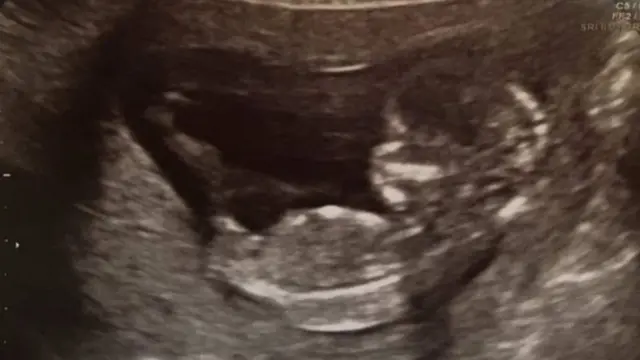

Umugore watwise inda 13 zivamo yabyaye umwana w'umukobwa nyuma y'akazi karimo ubuhanga bw'ibitekerezo bishya kakozwe n'impuguke mu by'uburumbuke.

Inda 11 Laura Worsley yasamye zagiye zivamo mu mezi atatu ya mbere yo gutwita, ariko yanasamye izindi nda ebyiri z'abana b'abahungu zavuyemo zimaze ibyumweru 17 n'ibyumweru 20.

Laura n'umugabo we Dave bo mu mujyi wa Kenilworth mu Bwongereza, bari bamaze inshuro 14 bagerageza kubona urubyaro, ku nshuro ya 14, bafashijwe na Porofeseri Quenby n'itsinda rye, babyara umwana w'umukobwa bise Ivy.

Nyuma yaho Laura yari amaze gufata imiti yo kugorora nyababyeyi, yongeye gusama ku nshuro ya 14.

Porofeseri Quenby yakoresheje imisemburo ("steriods") yo kuburizamo ubwirinzi bw'umubiri wa Laura kugira ngo inda ye ikomeze kumera neza kurenza ibyumweru 24 - igihe abana baba bafite amahirwe yo kubaho.